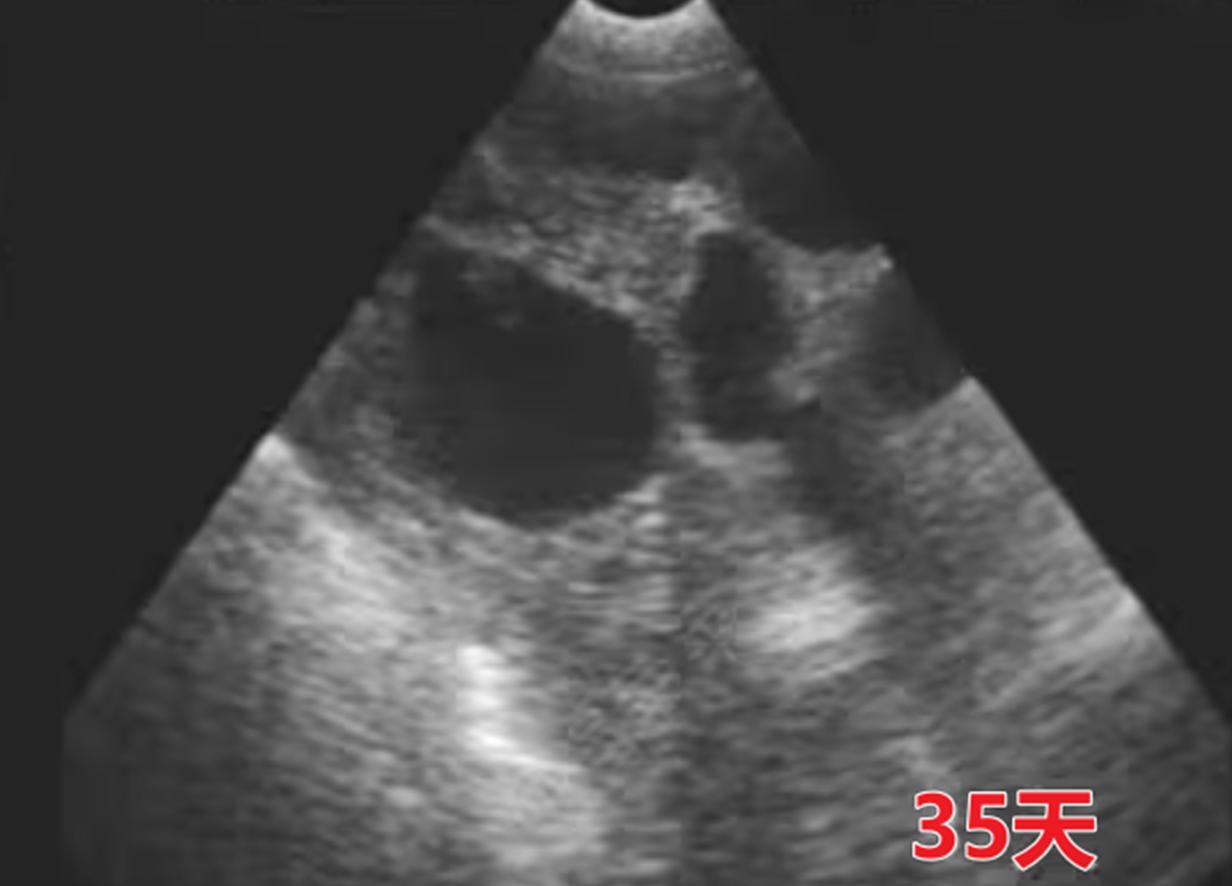

35天复检

此阶段主要是对前期检测结果的二次确认,操作流程相对简化:

由一名员工完成单批次母猪检测,重点关注上次检测时标记的 “不确定” 母猪,优先对这类母猪进行检测。

若确认妊娠则更新标记,若仍无法确定或确认空怀,需及时安排后续处理。